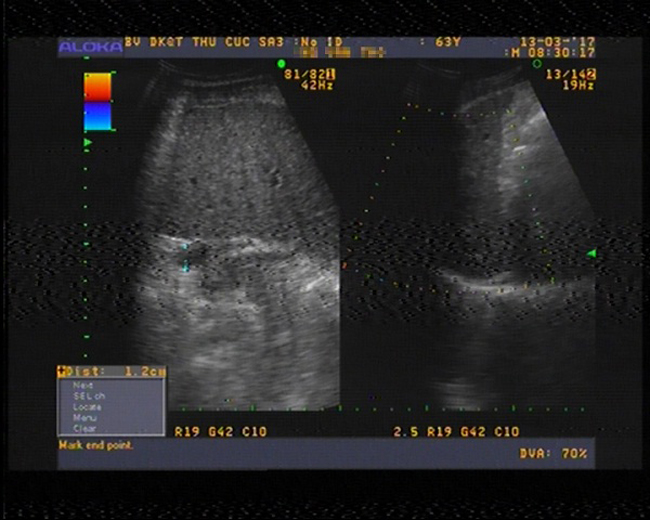

Sau 1 tháng điều trị, dịch trong ổ bụng của ông T. đã hết hoàn toàn

Sau một tháng điều trị bằng phương pháp hấp thu dịch, PGS. TS Thành cho biết bệnh dịch cổ trướng của ông T đã hết, chỉ số tiểu cầu tăng từ 37 lên 42 đơn vị, chỉ số Albumin trong máu tăng từ 23,8 lên đến 31,6 đơn vị, chỉ số men gan cũng tăng đáng kể,…